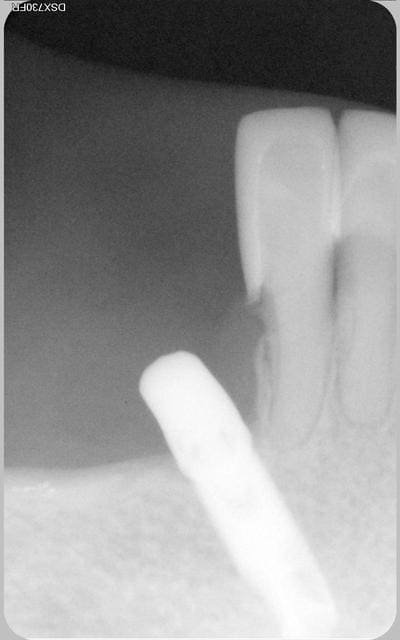

La patiente revenait de l'implantologiste. Je fais une radio de control et je vois ca. La patiente refusait toute prothèse.

Voilà le bébé

La patiente est revenue pour un soin a faire sur 35 qui est bien vivante.

cela fait excactement 9 ans, que l'implant a été posé.

Bien sur et c'est évident que le confrére implanto ne ferait plus ca maintenant.

deux implants dont un découvert fortuitement à la radio gengivo intégré sans vis de cicatrisation depuis a priori plus de 5 ans

ca a l'air d'être intégré...